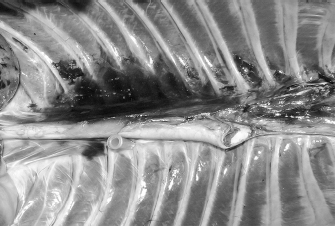

Fig. 2. Dorsal view of the thoracic cavity of a cat cadaver after a polyurethane foam injection after the removal of hepaxial and intercostal muscles. Despite the longitudinal subpleural spread, the foam surrounds the intercostal nerve only at the level of needle insertion site (arrow) and not at the adjacent spaces. The forceps are used to emphasize an intercostal nerve running above the endothoracic fascia, which appears almost completely intact in this subject.

During the preliminary phase, after post-injection anatomical dissection of the epaxial and intercostal muscles, the foam was observed to be directly in contact with the spinal nerves only at the level of the needle insertion site and not at the adjacent spaces. Cranially and caudally to the insertion point, in fact, the foam and the spinal nerves appeared separated by a thin connective layer identified as the endothoracic fascia (Fig. 2). The observed foam spread was identical between the two techniques used in this phase, and the surrounding connective tissues were intact. These findings allowed us to move to the second phase, assuming that the spread obtained after probing the TPVS could be used as a clinical model.